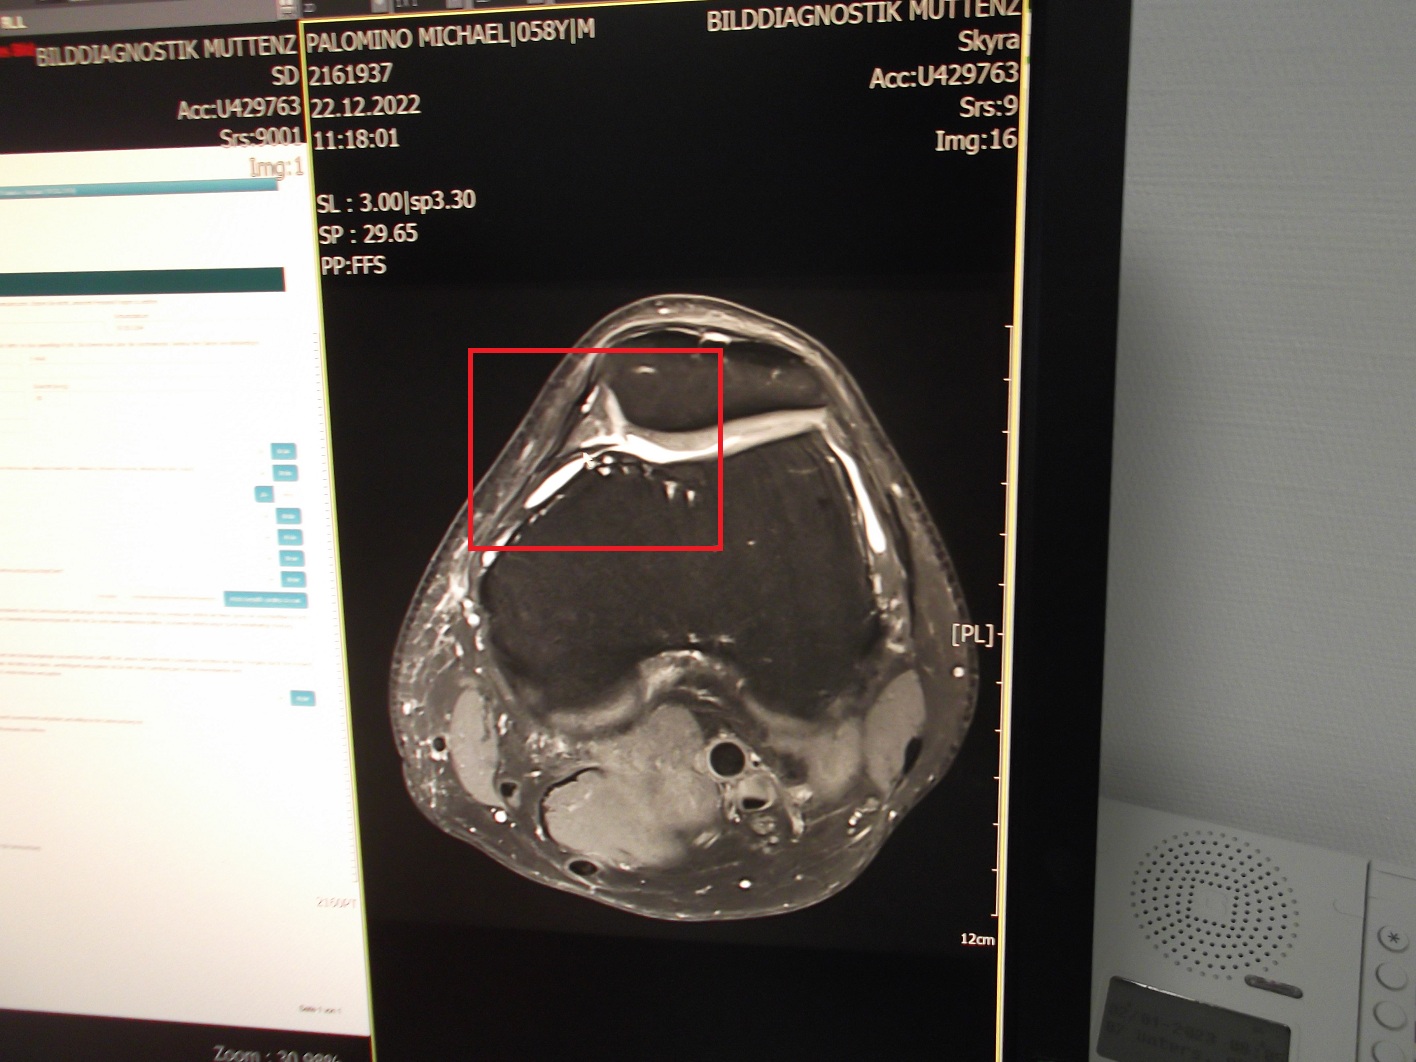

Plica mediopatellaris, MRT vom 22.11.2022 [1] - Knie Schema mit dem Querschnitt [x1]

Plica mediopatellaris, MRT vom 22.11.2022 [1]

[1] Foto mit Plicasyndrom von Michael Palomino 2022